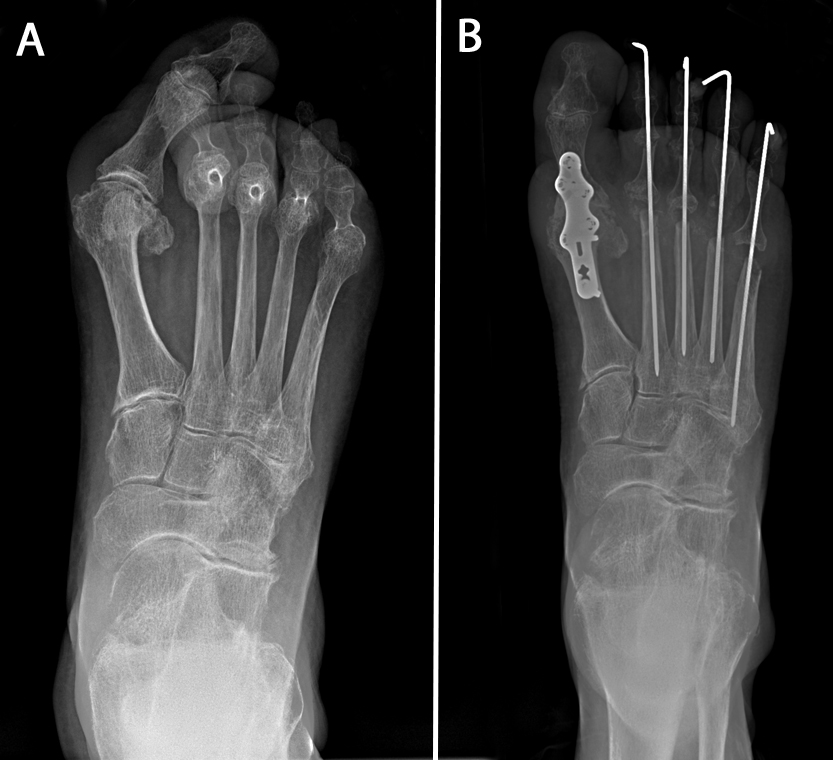

(Left) In this X-ray, RA has caused the big toe to cross over the second toe — a typical appearance of a bunion. The smaller toes are dislocated, resulting in painful and severe claw toes. (Right) This X-ray taken immediately after fusion of the big toe shows that the prominent bones on the ball of the foot were removed and the claw toes were corrected. Pins hold the toes in place while the soft tissues heal. The pins are removed in the office after 4 to 6 weeks with minimal discomfort.